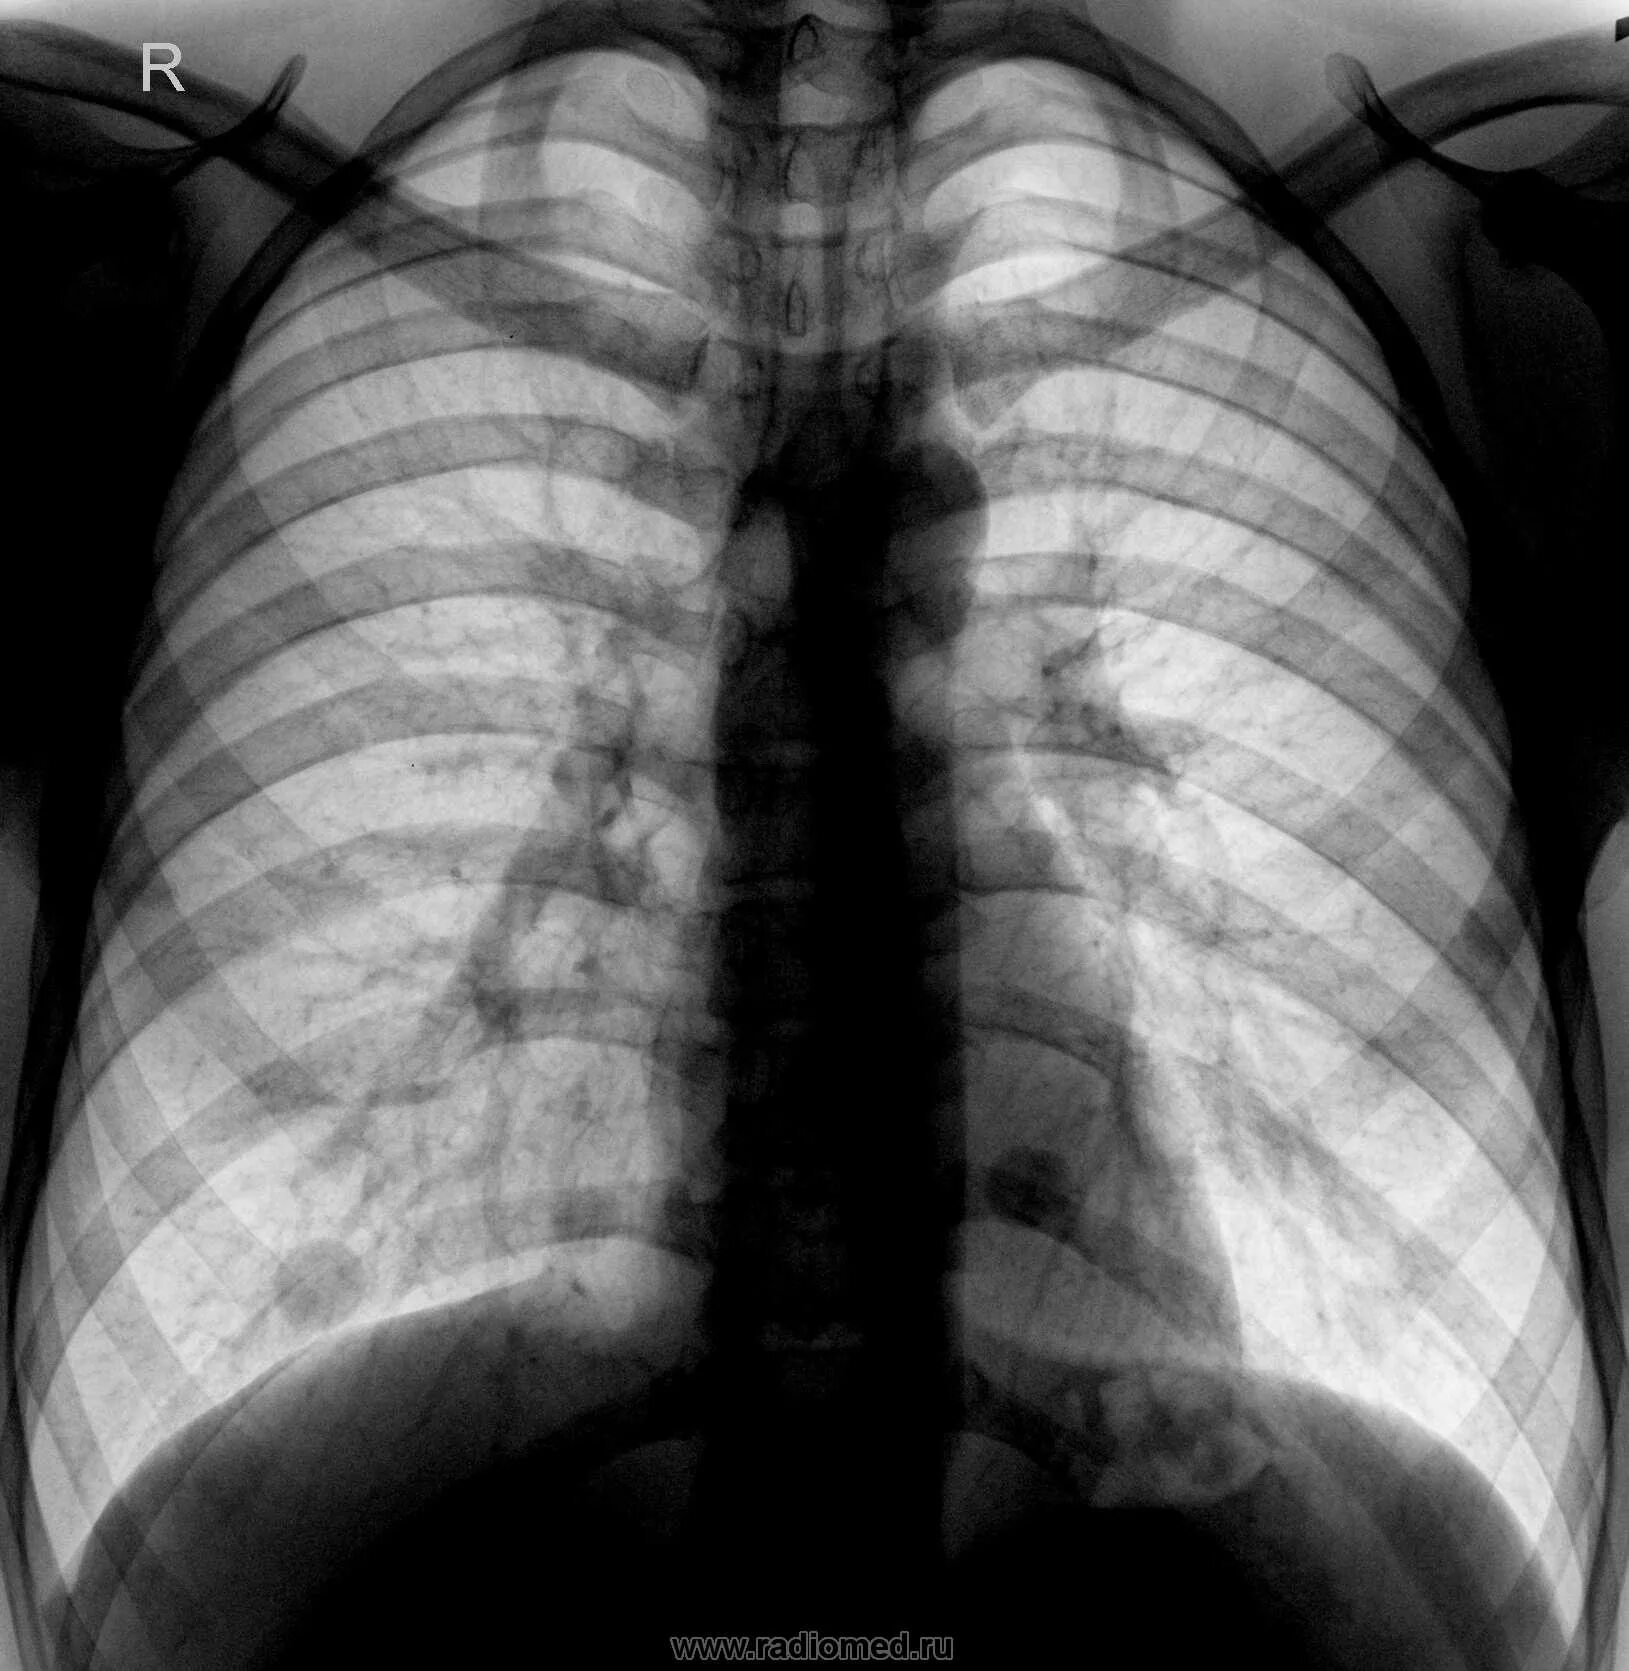

Почему метастазы в легких